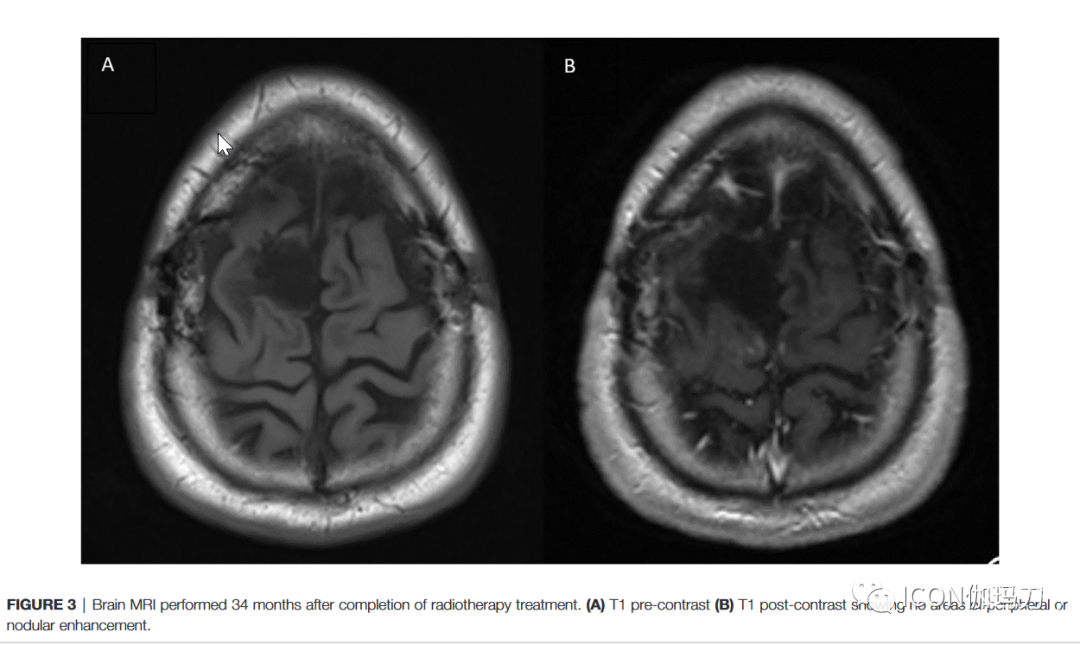

完成巩固性SBRT 3个月后的MRI显示硬膜下积液和硬膜强化结节覆盖右额叶后部,尺寸为0.3 x 0.7 cm。同时的神经外科随访没有发现临床变化。此后大约每3个月的MRI和临床随访显示无新证据显示疾病复发,且强化逐渐消退。放射外科治疗结束后34个月进行的最新的脑MRI显示,只有预期的胶质细胞增生,术后改变,没有强化的病灶或肿瘤复发的证据(图3)。患者在完成治疗后仍无症状,无任何功能障碍。

图3放疗结束后34个月脑部MRI。(A) T1平扫(B) T1增强后未见周边或结节强化区域。